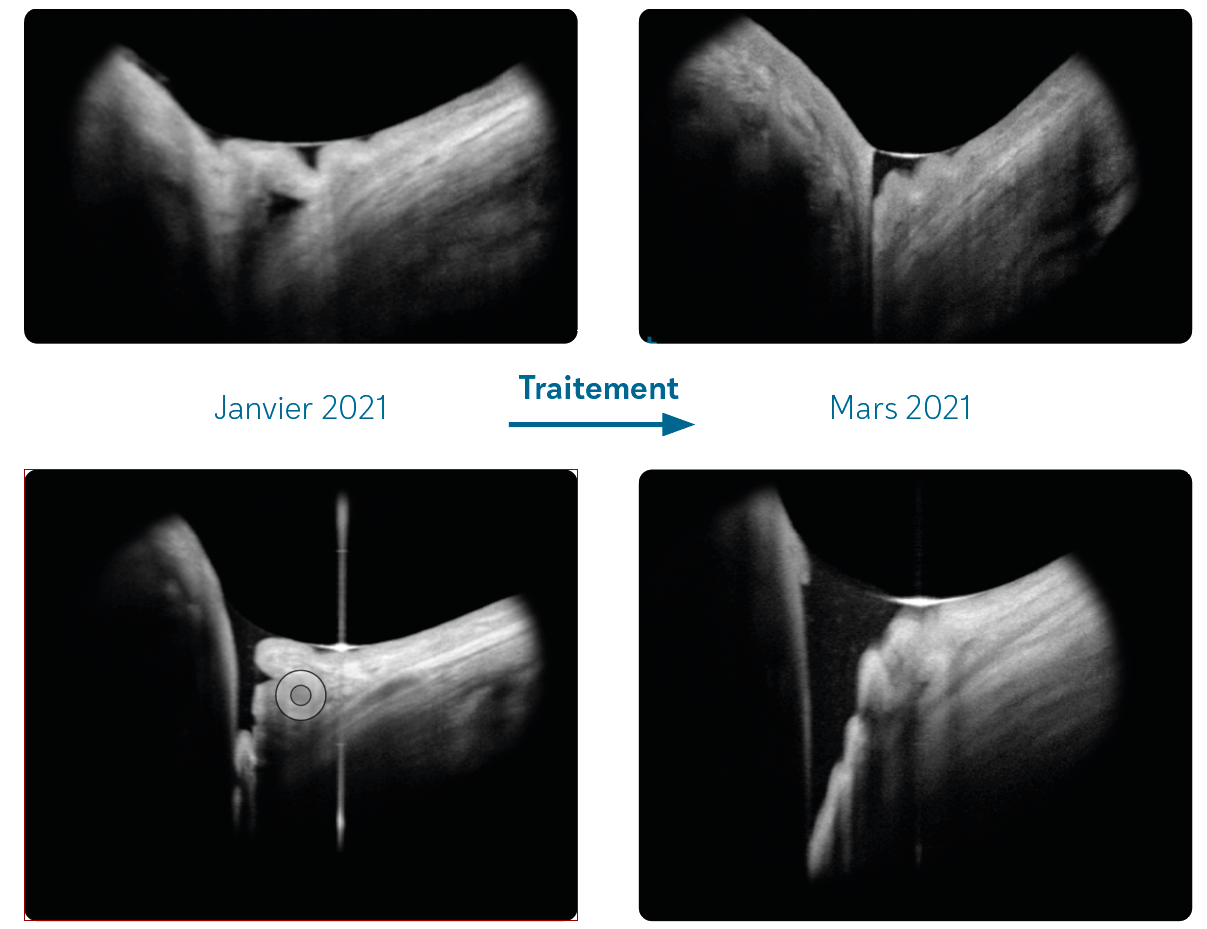

Figure 3. Imagerie multimodale d’une patiente de 34 ans atteinte de PIC. Le panneau (A) montre une photographie en couleur du fond d’œil d’un œil à aspect myopique, présentant des zones d’atrophie en plaques et de multiples lésions de PIC. (B) L’angiographie à la fluorescéine révèle plusieurs foyers hyperfluorescents au pôle postérieur. Le panneau (C) montre une coupe OCT à travers ces zones : en position sous-fovéolaire (pointe de flèche), on observe une lésion active caractérisée par un dédoublement du complexe membrane de Bruch–EPR, une rupture de la membrane de Bruch, une hypertransmission choroïdienne et un épaississement choroïdien ; à l’inverse, une lésion inactive adjacente (étoile) se caractérise uniquement par une interruption du complexe membrane de Bruch–EPR avec hypertransmission choroïdienne. Le panneau (D) montre une angiographie au vert d’indocyanine en phase tardive, avec une ligne hypofluorescente ramifiée compatible avec des lacquer cracks (étoile). Le panneau (E) montre l’autofluorescence du fond d’œil au niveau du pôle postérieur, où les lésions actives apparaissent comme des zones de légère hyperautofluorescence (pointe de flèche), tandis que la cicatrice atrophique centrale apparaît hypoautofluorescente.